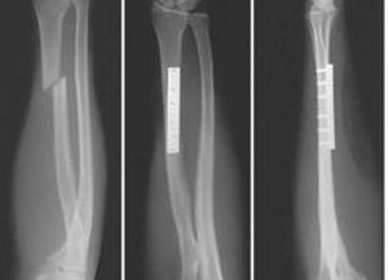

РОЗПІЗНАЙТЕ КІСТКУ. ПЕРЕЛОМ ЯКОЇ ЇЇ ЧАСТИНИ ВИ БАЧИТЕ НА РЕНТГЕНОГРАМІ?

варіанти відповідей

ULNA

RADIUS

FEMUR, ШИЙКА

ПРОКСИМАЛЬНОГО ЕПІФІЗА

ДИСТАЛЬНОГО ЕПІФІЗА

ДІАФІЗА

ЛІКТЬОВОГО ВІДРОСТКА

ПРОМЕНЕВОГО ВІДРОСТКА